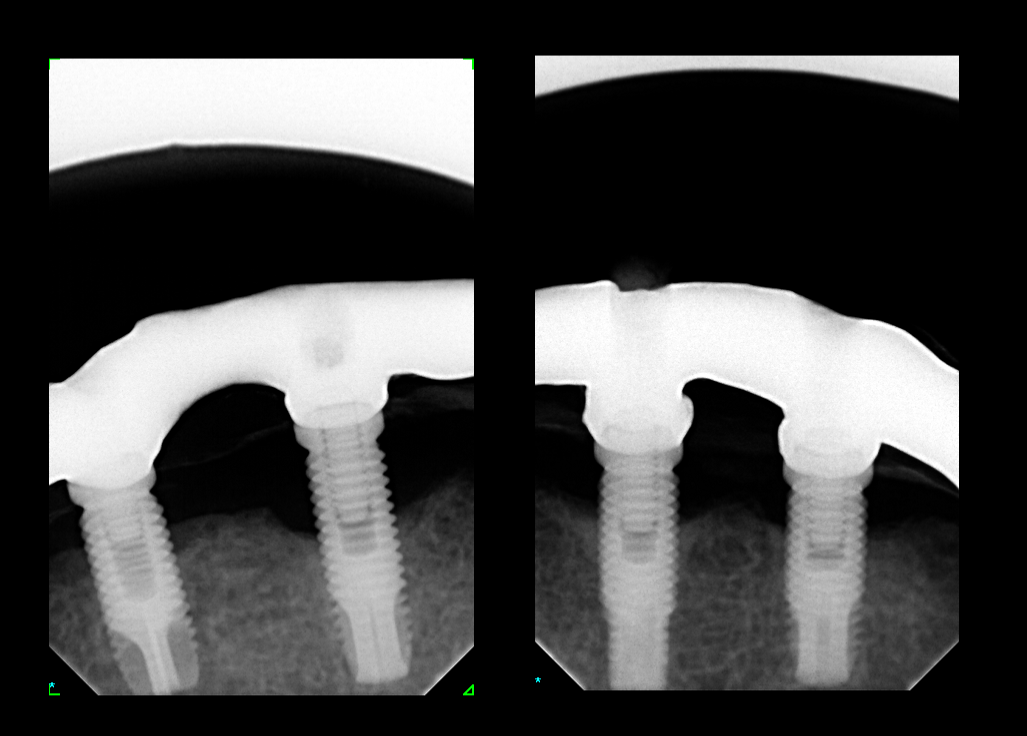

Buenas tardes, agradeceria que me ayudaran a indentificar esos 2 implantes para poder rehabilitarlos. Muchas gracias Un saludo!